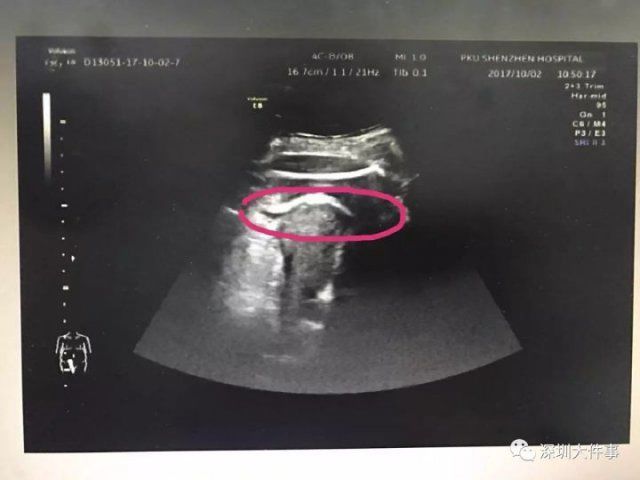

医生初步怀疑患者子宫破裂,当即安排做了 B 超。检查发现,胎儿的一条腿 " 踢破 " 了子宫,进入了腹腔,大腿根正卡在子宫壁上!

▲红色圆圈处是胎儿的腿,已经伸到子宫壁外

医生追问患者病史,原来张女士2016 年做过子宫肌瘤剔除术,术后半年就怀孕了。不到 2 分钟 B 超检查,仅凭有限病史,医生快速作出诊断:高度怀疑为疤痕子宫破裂